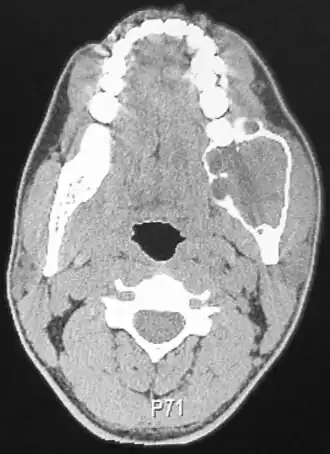

![]() Компьютерная томография амелобластомы | |

Амелобластома — доброкачественная опухоль, происходящая из эпителия зубного сосочка[1], клеточных элементов эмалевого органа или дериваты его глубоких слоев — клеток Малассе и Серре.

Различают солидную и кистозную форму заболевания, при новообразованиях значительной величины процесс распространяется на окружающие мягкие ткани.

Кистозная форма представлена значительным количеством пустот мультицикличного характера, разделенных перегородками из костной ткани. Изредка кистозная форма адамантиномы может быть однокамерной, заключая в себе непрорезанный зуб, напоминая фолликулярную кисту; однокамерность при этом обусловлена слиянием кистозных полостей. Челюсть в месте патологии деформируется, лицо становится асимметричным в дистальных отделах. Периостальная реакция, как правило, отсутствует, зубы не смещены. Прозрачность тени многокамерной опухоли неоднородная, максимальная — в центре, иногда наблюдаются воспалительные осложнения в одной из кист, эрозии корней, в отличие от остеобластокластомы, не наблюдается.

При солидной форме визуализируется округлой или овальной формы одиночное просветление преимущественно в области угла нижней челюсти. Дифференцировать солидные адамантиномы следует исходя из эпителиальных кист и дрибносотистых образований, в частности остеобластокластомы.